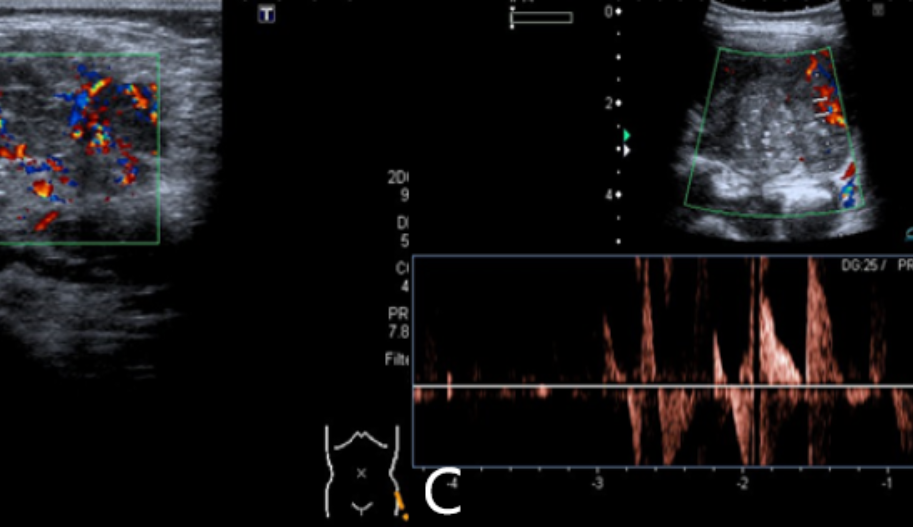

Mass Lesion Color Doppler Ultrasound

The growth of malignant tumors largely depends on the blood supply provided by new vessels, which develop under the tumor’s angiogenic stimulation. These new vessels penetrate the lesion.

The course and distribution of these vessels within the tumor are chaotic and irregular, with multiple anastomoses and shunts. The irregular course of these vessels can be identified by their abnormal flow in color Doppler and detected through wave pattern analysis with high speed and/or low resistance.

Abnormal flow has also been identified in malignant tumors originating from soft tissues.

Doppler ultrasound devices have high sensitivity in detecting the presence and identification of blood flow.